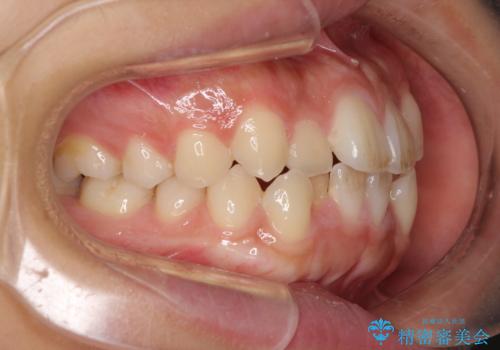

- 前歯のデコボコと口元の突出感を気にして来院された患者様です。

上下左右第一小臼歯4本を抜歯し、ワイヤー装置にて口元を引っ込めるよう矯正治療を行うこととしました。

非常にスムーズに歯列移動が行われ、当初は2-2.5年を予想していましたが、僅か1年4ヶ月で治療を終えることができました。